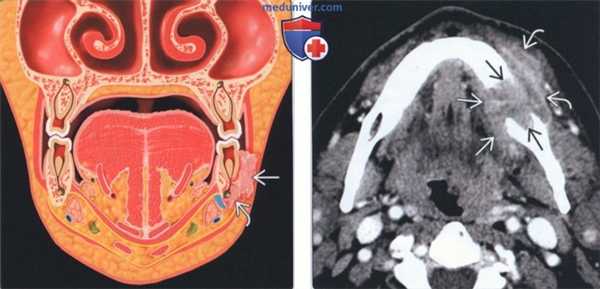

(Слева) На рисунке показан ПКР десны нижней челюсти, прорастающий тело нижней челюсти, что соответствует стадии Т4a. Обратите внимание на вовлечение нижнего альвеолярного нерва - важный момент для полной резекции.

(Справа) На аксиальной КТ с КУ определяется неоднородная опухоль с деструкцией тела нижней челюсти. Опухоль распространяется кнаружи, вовлекая деснево-щечную борозду и щеку, и кнутри, поражая дно полости рта. Опухоль на стадии T4aN1 была полностью удалена с реконструкцией композитным лоскутом.